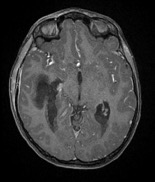

Figure 2. Axial T2 flair magnetic resonance imaging demonstrated a right temporal lobe abscess.

Figure 4. Postcontrast axial magnetic resonance imaging demonstrated (a, top) mastoiditis and (b, bottom) a right temporal lobe abscess decompressing into the ventricular system, with presence of ventricular abscesses.